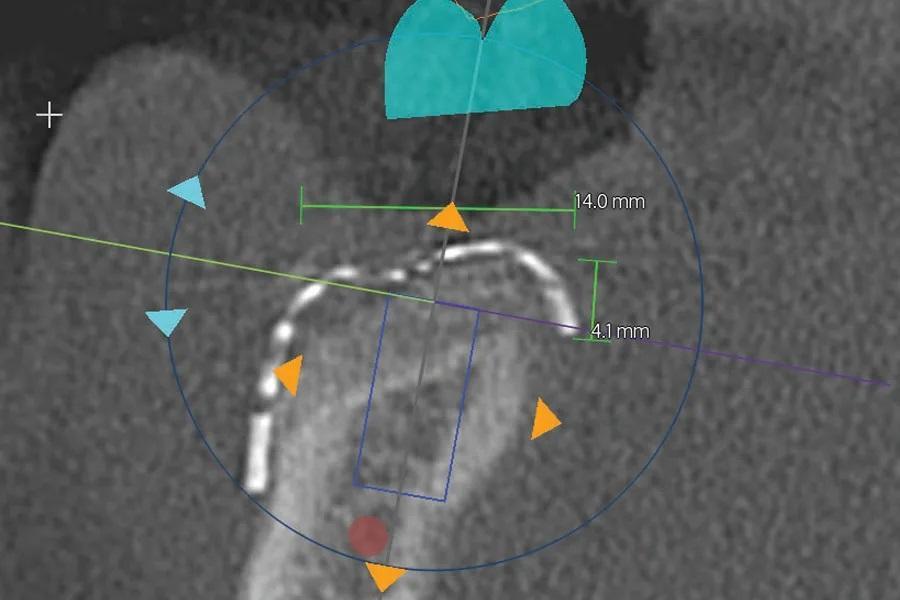

Послеоперационный период прошел без осложнений. КЛКТ, выполненная через 6 месяцев, показала формирование зрелой костной ткани под сеткой в запланированных местах установки имплантатов (Фото 5–7).

Фото 7. Корональный срез КЛКТ в области запланированного имплантата первого моляра правой нижней челюсти (наклонный синий прямоугольник в центре изображения). Зеленые линии и соответствующие числа указывают вертикальные и горизонтальные измерения аугментированной кости: 4,1 мм и 14 мм соответственно.